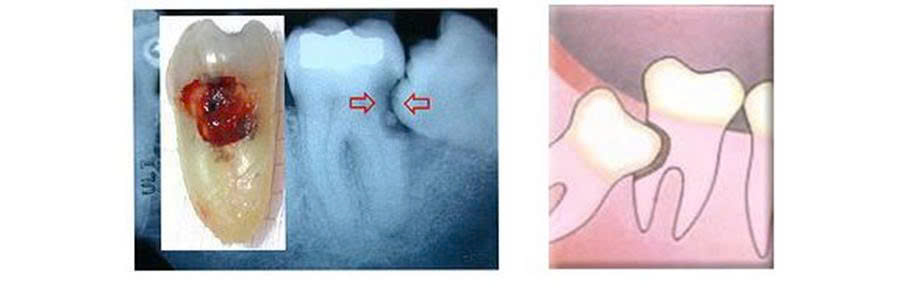

Hình 1. Một số hình ảnh răng khôn hàm dưới

Răng khôn còn gọi là răng số 8 hay răng hàm lớn thứ ba, là răng mọc cuối cùng, thường mọc ở độ tuổi trưởng thành từ 18 đến 25 tuổi, đôi khi có thể mọc sớm hơn hoặc muộn hơn. Đây là răng hay gây nhiều đau đớn và biến chứng nhất trên cung hàm do thường hay mọc lệch, ngầm hoặc kẹt.

Răng lệch là thuật ngữ chỉ tình trạng răng không mọc ở vị trí bình thường trên cung răng sau khi hết thời kỳ mọc bình thường. Nó có thể mọc lệch ở các tư thế như: lệch gần, lệch xa, lệch trong, lệch ngoài.

Răng ngầm là răng không mọc được bình thường, vẫn còn trong xương hàm, không thấy trong khoang miệng.

Răng kẹt là răng bị cản trở về mặt cơ học do xương hay răng lân cận dẫn đến sự mọc răng không bình thường.

Hình 2. Răng khôn hàm dưới và răng khôn hàm trên mọc lệch, ngầm.